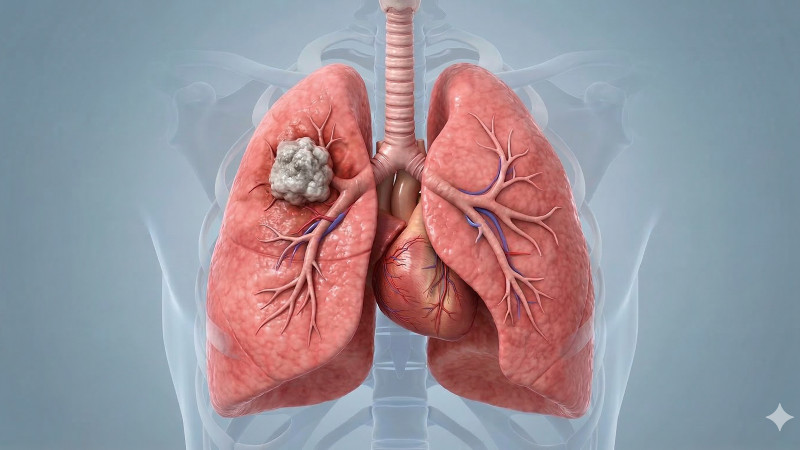

Tomáš Řehoř (57) z Prahy, bývalý kuřák, podstoupil preventivní vyšetření na doporučení lékařky, které odhalilo nezhoubný nádor na plicích, ačkoliv neměl žádné potíže, což dokazuje důležitost včasného screeningu rakoviny plic. #screeningrakoviny #zdraví #prevencetruchu #dobrezpravy

Rok co rok je rakovina plic odhalena u více než 6500 pacientů, přičemž pouze u jednoho z deseti je diagnóza stanovena včasné léčitelném stádiu, přičemž preventivní screening pomůže každému druhému vyšetřenému, avšak polovina oslovených na něj nedochází a praktický lékaři tento vyšetřovací program nabízejí jen polovině svých pacientů. #rakovinaplic #screening #prevencetumoru